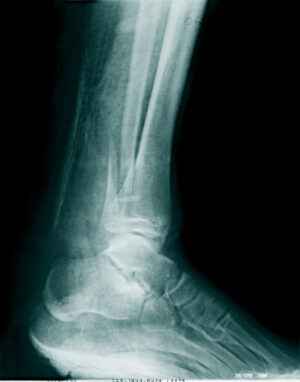

Bone cement and bone adhesives are commonly used during fracture repair to help hold bone fragments in place so that they can naturally fuse together throughout the healing process. However, bone glue is oftentimes paired with the implementation of surgical hardware, to further stabilize the fracture site and prevent bone shifting. Researchers say their new bone glue may be so effective that hardware insertion isn’t needed for many fractures.

According to reports, the bone glue has tested well when it comes to both safety and effectiveness, and has been tested on over 150 patients. Additionally, researchers stated that the glued bones showed a maximum force bonding of over 400 pounds, a shear strength of about 0.5 MPa, and a compressive strength of around 10 MPa. While those measurements may not mean much on their own, researchers say that it means the glue has the potential to replace traditional metal implants in fixation operations. Widespread adoption also has the potential to reduce the risk of hardware reaction or infections.